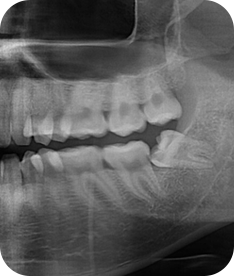

청담네오플란트는 3D CT 촬영 후 전문의료진들의 정확한 분석으로 안전하게 사랑니를 발치합니다.

01. CT 촬영

안전하고 통증을 최소화한 발치를 위해 3차원 정밀 분석을 합니다.

02. 정확한 분석

사랑니의 크기와 방향, 깊이, 뿌리 상태 등과 구강검진을 실시합니다.